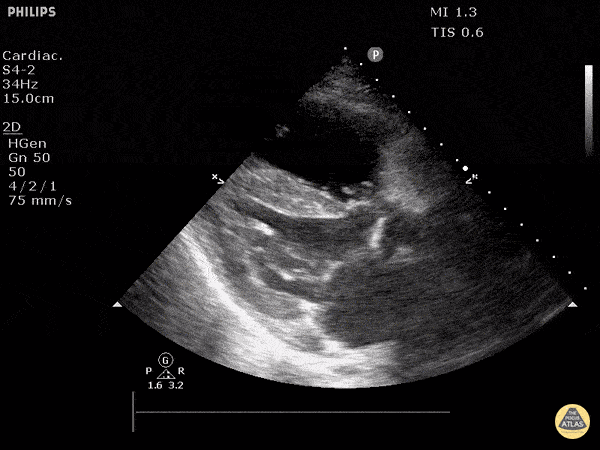

https://www.thepocusatlas.com/right-ventricular-dysfunction

View: Unspecified Parasternal Long Axis Parasternal Short Axis Apical Four-Chamber Subcostal Four-Chamber Subcostal Inferior Vena Cava Right Upper Quadrant Left Upper Quadrant Suprapubic Longitudinal Suprapubic Transverse Subxiphoid Anterior Thoracic Phrenic